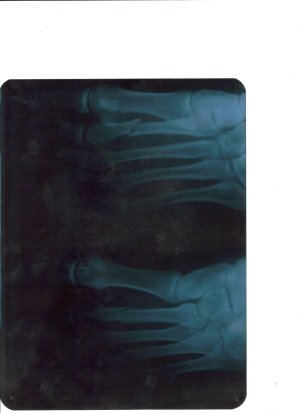

Добрый день. Случился у меня 22марта2011года перелом второй плюсневой кости ( просто шел быстрым шагом по улице и почувствовал боль ) через полторы недели обратился к травматологу, сделали снимок и увидили перелом второй плюсневой кости со смещением.

Доктор сказал что смещение слабое, и наложил "СКОТЧ" - это как гибс только меньше,легче, и как гибс негнется. Доктор сказал что в месте перелома образуется костный мозоль через 3-4 недели, а через 6 недель со дня наложения скотча его снимут, а ставить спицы нельзя, так как в даном случаее они ненужны и могут принести больший вред.

Так вот мой вопрос адресуется всем знающим , и вправду ли через 3-4 недели образуется костный мозоль? ДА И ВООБЩЕ ИНТЕРЕСУЕТ ВАШЕ МНЕНИЕ ПО ЭТОМУ ПЕРЕЛОМУ.

Доктор сказал что смещение слабое, и наложил "СКОТЧ" - это как гибс только меньше,легче, и как гибс негнется. Доктор сказал что в месте перелома образуется костный мозоль через 3-4 недели, а через 6 недель со дня наложения скотча его снимут, а ставить спицы нельзя, так как в даном случаее они ненужны и могут принести больший вред.

Так вот мой вопрос адресуется всем знающим , и вправду ли через 3-4 недели образуется костный мозоль? ДА И ВООБЩЕ ИНТЕРЕСУЕТ ВАШЕ МНЕНИЕ ПО ЭТОМУ ПЕРЕЛОМУ.